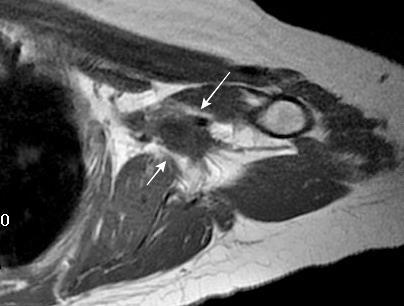

Tumor desmoide (“Fibromatosis agresiva”)

T1: Isointensos con músculos.

T2: Señal intermedia y de alta intensidad.

Presencia frecuente de áreas curvilíneas y lineales dentro de la lesión

Mansour J et al. Diagnostic and Imaging Approaches to Chest Wall Lesions. Radiographics 2022